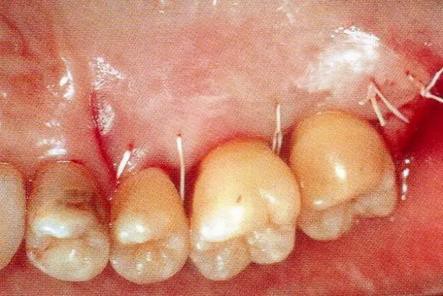

▼圖13-5 通過垂直褥式縫合法進行緊密的縫合。

▼圖13-6 術(shù)后8個月的狀態(tài)。牙周探診值改善到4mm,牙齦萎縮基本沒有出現(xiàn)。進行GTR法時,上頜顎側(cè)牙齦容易出現(xiàn)壞死,但是使用EMD促生長因子處理時,不容易出現(xiàn)牙齦壞死和退縮。